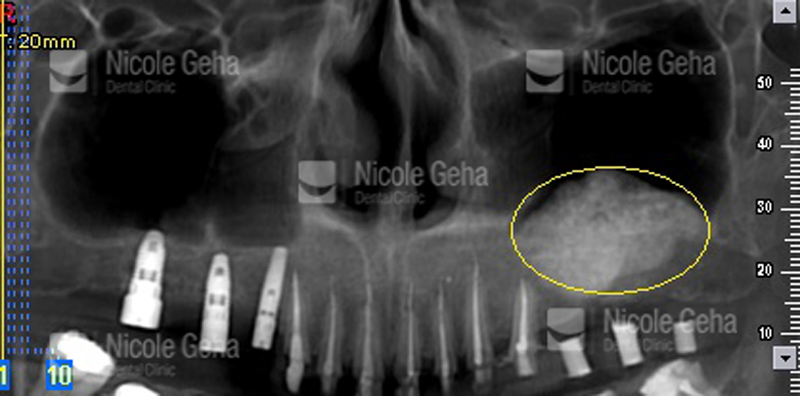

A sinus lift, also called sinus augmentation or sinus elevation, is a bone augmentation procedure in the area of your molars and premolars, when you have insufficient natural bone for dental implant placement. To make room for the bone, the sinus membrane has to be moved upward, or “lifted”.

Contrary to this so-called external sinus lift, the sinus elevation locally at the site of implantation is referred to as internal sinus lift.

EXTERNAL SINUS LIFT

INTERNAL SINUS LIFT